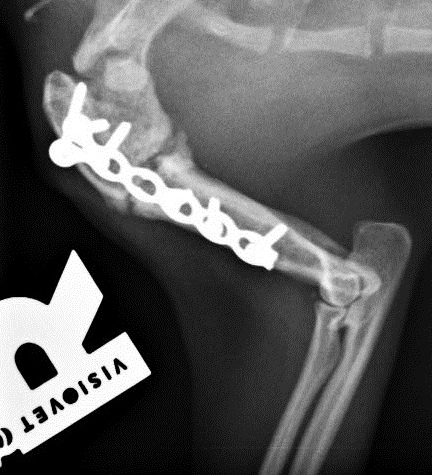

Die kleine verschmuste Maus ist so tapfer, inzwischen hat sie bereits beide OPs gut überstanden. Bei der ersten OP wurde die Biegung im Oberarm herausgeschnitten und der Oberarm in gestreckter Position mit einer Platte befestigt. Die Röntgenkontrolle hat gezeigt, dass der Knochen schon gut verheilt ist, Ariel kann damit sogar schon wieder ganz gut laufen. So konnte also auch schon die zweite OP stattfinden, bei der ihr luxiertes linkes Schultergelenk in eine normale Position gebracht und die Bänder gestrafft wurden.

Direkt nach der OP:

...und schon fast verheilt!